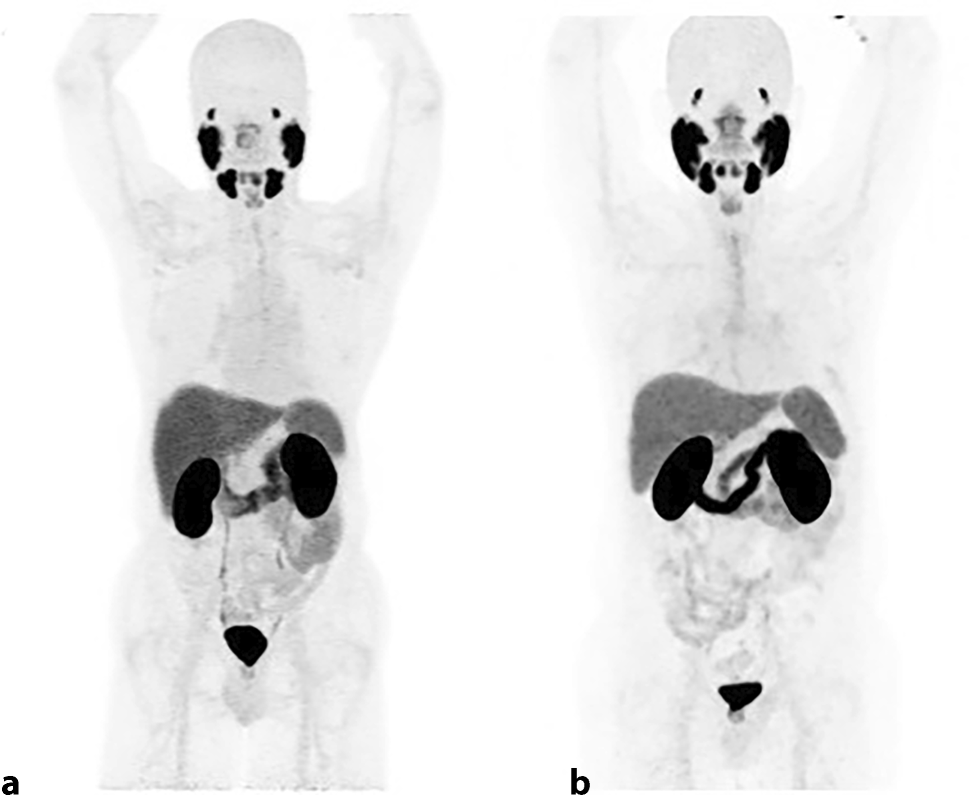

Fig. 1

Physiological biodistribution on maximum intensity projection (MIP) images of both prostate-specific membrane antigen (PSMA)-targeted positron emission tomography (PET) scans with (a18F‑DCFPyL and (b68Ga-PSMA-11